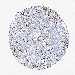

Basal cell and squamous cell cancer

SKIN CANCER - Protein expressioni

A mouse-over function shows sample information and annotation data. Click on an image to view it in a full screen mode. Samples can be filtered based on level of antibody staining by selecting one or several of the following categories: high, medium, low and not detected. The assay and annotation is described here.

Antibody stainingi

Antibody staining in the annotated cell types in the current human tissue is reported as not detected, low, medium, or high, based on conventional immunohistochemistry profiling in selected tissues. This score is based on the combination of the staining intensity and fraction of stained cells.

Each image is clickable and will lead to virtual microscopy that enables deeper exploration of all samples and also displays staining intensity scores, fraction scores and subcellular localization as well as patient and tissue information for each sample.

Antibody HPA039343

Antibody HPA040048

Squamous cell carcinoma, NOS